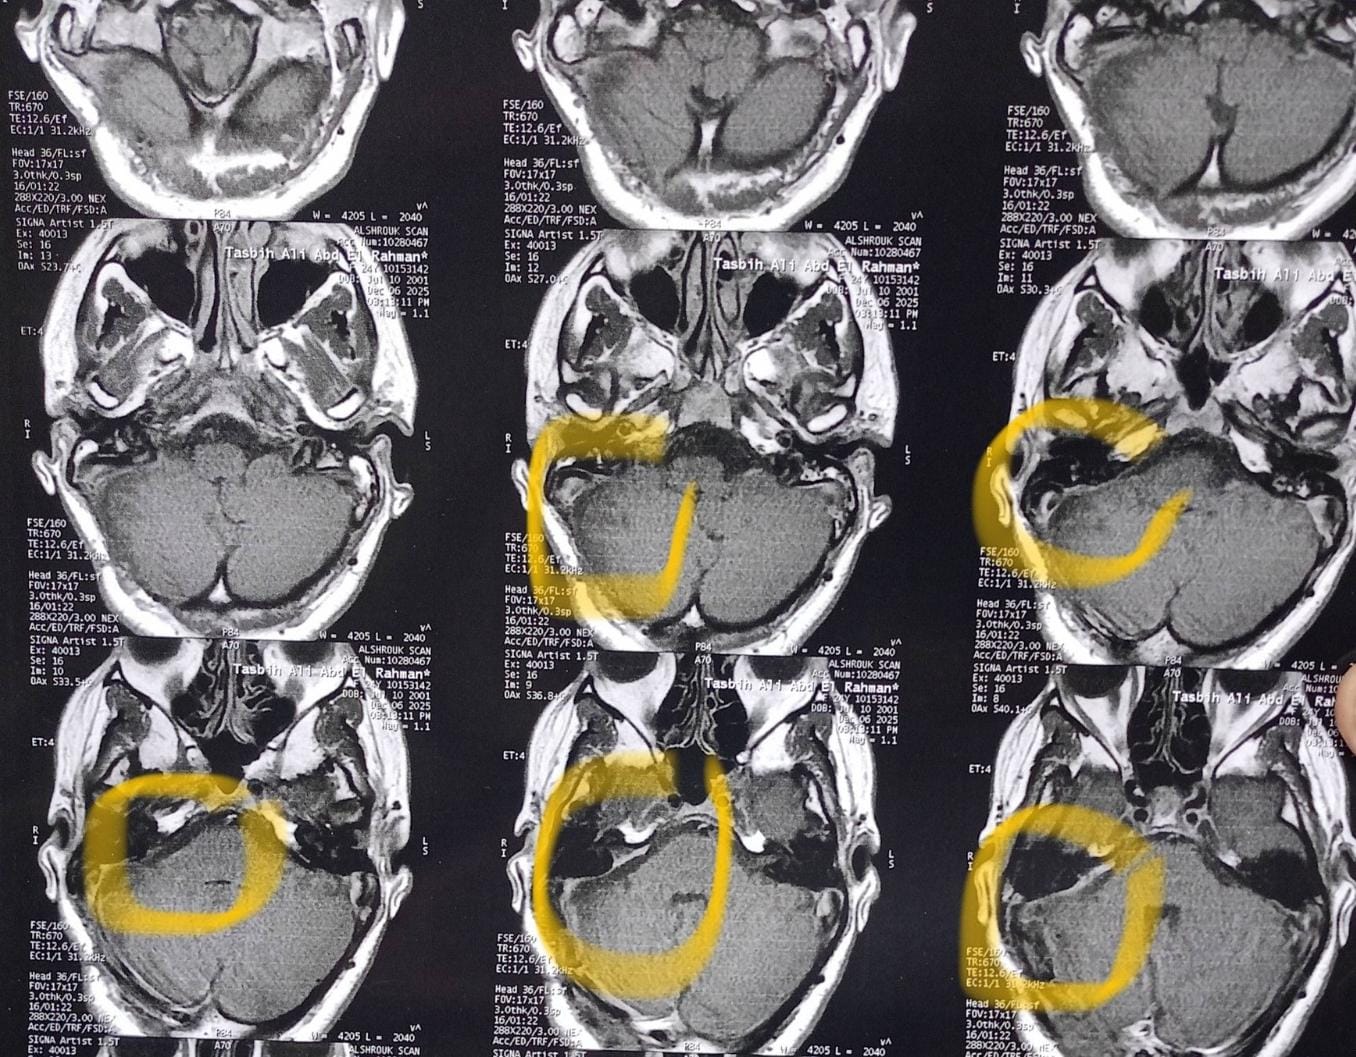

أورام الزاويه المخيخيه

بعد

قبل